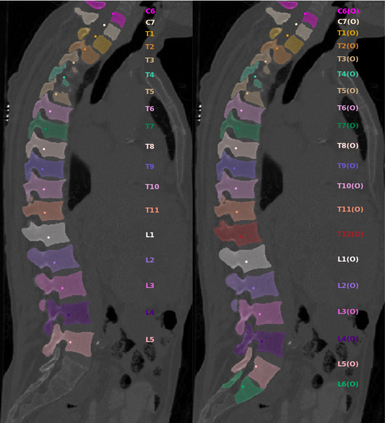

Vertebrae localization, segmentation and identification in CT images is key to numerous clinical applications. While deep learning strategies have brought to this field significant improvements over recent years, transitional and pathological vertebrae are still plaguing most existing approaches as a consequence of their poor representation in training datasets. Alternatively, proposed non-learning based methods take benefit of prior knowledge to handle such particular cases. In this work we propose to combine both strategies. To this purpose we introduce an iterative cycle in which individual vertebrae are recursively localized, segmented and identified using deep-networks, while anatomic consistency is enforced using statistical priors. In this strategy, the transitional vertebrae identification is handled by encoding their configurations in a graphical model that aggregates local deep-network predictions into an anatomically consistent final result. Our approach achieves state-of-the-art results on the VerSe20 challenge benchmark, and outperforms all methods on transitional vertebrae as well as the generalization to the VerSe19 challenge benchmark. Furthermore, our method can detect and report inconsistent spine regions that do not satisfy the anatomic consistency priors. Our code and model are openly available for research purposes.